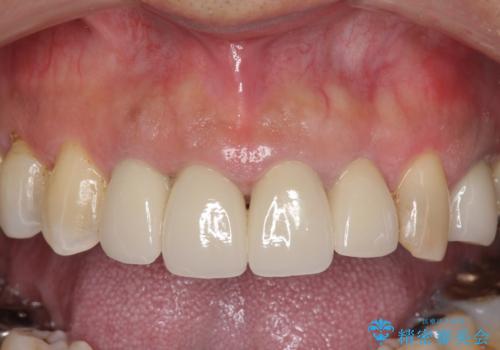

老朽化した前歯のクラウンやりかえ

- 10数年前に治療した上顎前歯のクラウンをやり替え、審美性を回復したいと希望され来院されました。

X線写真より問題のなかった根管治療は行わず、クラウンを除去し仮歯でを装着したのちジルコニアクラウンを製作していきます。

- 48.4万円(税込)(仮歯・ジルコニアクラウン×4)費用は治療当時の料金となります